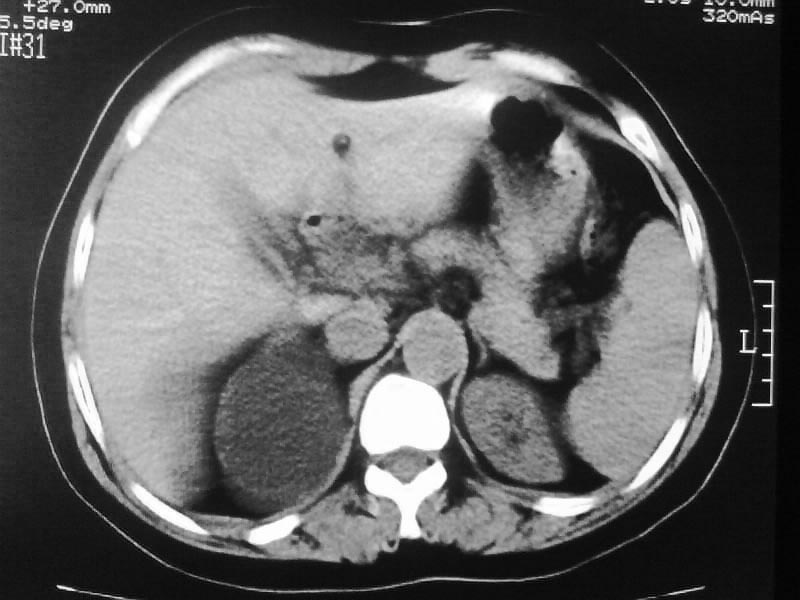

标题: CT20044:女,45岁,腰痛2年,双肾结石,右输尿管结石,右肾重度积 [打印本页]

标题: CT20044:女,45岁,腰痛2年,双肾结石,右输尿管结石,右肾重度积

支持双肾结石、右输尿管上端结石,右肾重度积水

双肾结石、双输尿管结石并右肾积水。

双肾,输尿管结石,右肾重度积水。